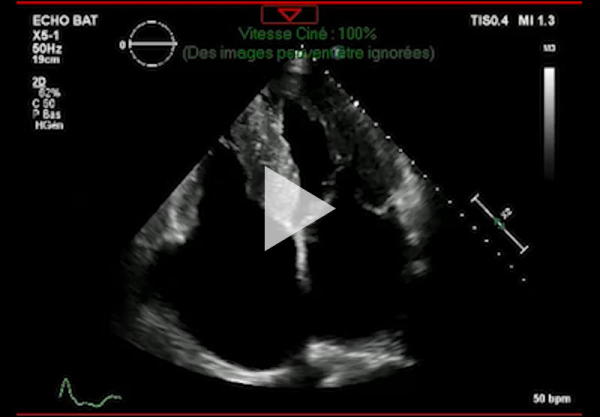

Vidéo 4 - Échocardiographie 2D en incidence apicale 4 cavités

- Ventricule gauche non dilaté, hypertrophie concentrique symétrique majeure non-obstructive, hypokinésie globale, aspect scintillant du myocarde

- FEVG 45- 50 %

- Pressions de remplissage VG probablement élevées

- Dilatation bi-atriale marquée (OG 54 ml/m²)

- Fuite mitrale centrale modérée, épaississement des valves

- Ventricule droit non dilaté modérément hypertrophique

- Fonction systolique VD diminuée

- Hypertension pulmonaire peu probable (Vmax IT 2,85 m/s)

- Décollement péricardique minime inférieur